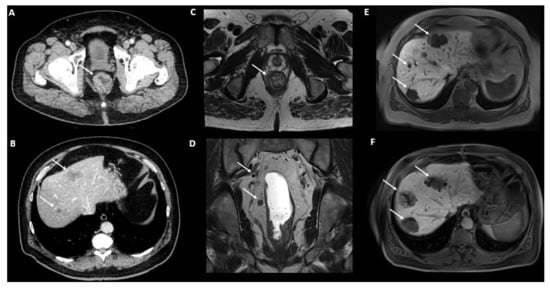

2.5.2. Magnetic Resonance Imaging (MRI)